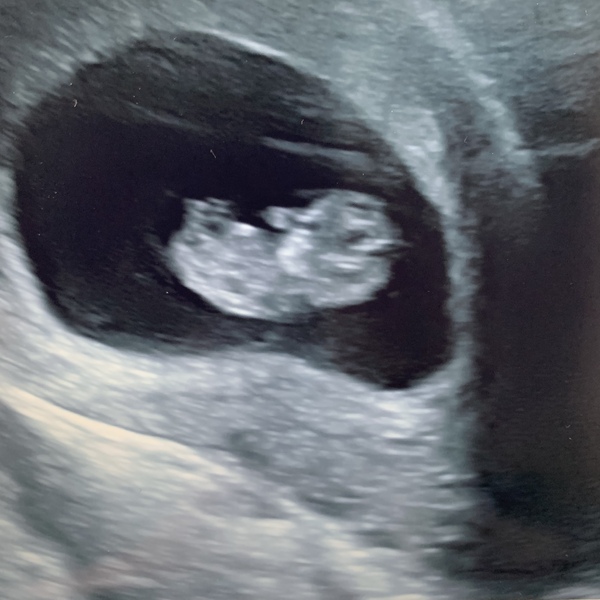

Hi all! Off to catch up in a mo but just wanted to check in - just back from our scan and little bean was wriggling away on the screen with a nice strong heartbeat and measuring exactly nine days on from my scan nine days ago. That makes me 9+6 today, annoyed about losing a day from my date based on LMP mainly because I wanted to be over 10 weeks but close enough! So thrilled, was amazing seeing the little one just wriggling around and for my husband to be able to be there, too. I know we still have a long journey ahead of us but I’m feeling a little bit more confident about it - we’ve got past last time and everything feels much easier (last time I measured a week behind, which I do actually think was right based on when I thought I ovulated and I also had a ‘collapsed corpus luteum’ that I was told not to worry about by the private scan place but never actually got any answers from midwives about). Sonographer said she couldn’t see any signs of any bleeds or cysts or anything so last week’s bleed must have just been one of those things 🤷🏻‍♀️

We went to Window to the Womb this time and I would 100% recommend them. Last time we went to Ultrasound Direct and the experience was nowhere near as positive.

So overall, I’m thrilled and a little bit in love 🥰 Just hoping baby bean holds on now and it’s not too long until my 12 week scan 🤞🏼

@SkyBlue20 that's a great pic! 😍 glad everything went well 😀😀xx

I love your scan picture it makes me so happy 😊😊